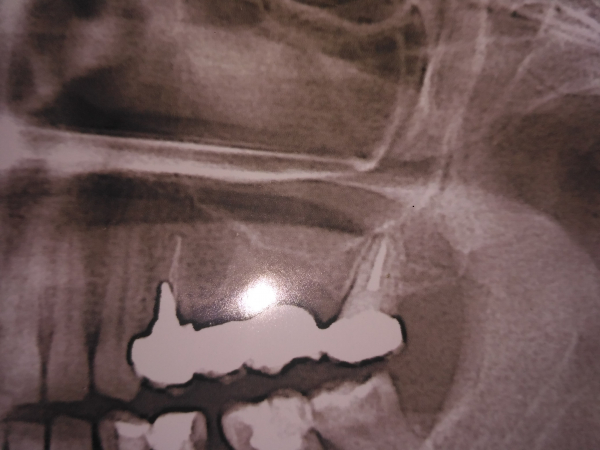

У меня немного воспалилась десна в районе моста. Мост держится на пролеченном зубе. Сделала снимок, запломбировано все идеально, каналы тоже, но он потемнел снизу с внутренней стороны и десна болит. Сказали вроде как накусана. Сказали, что мост нужно только распиливать и ставить новый. Мост, где то на 3 зуба.

Прикрепленые фото